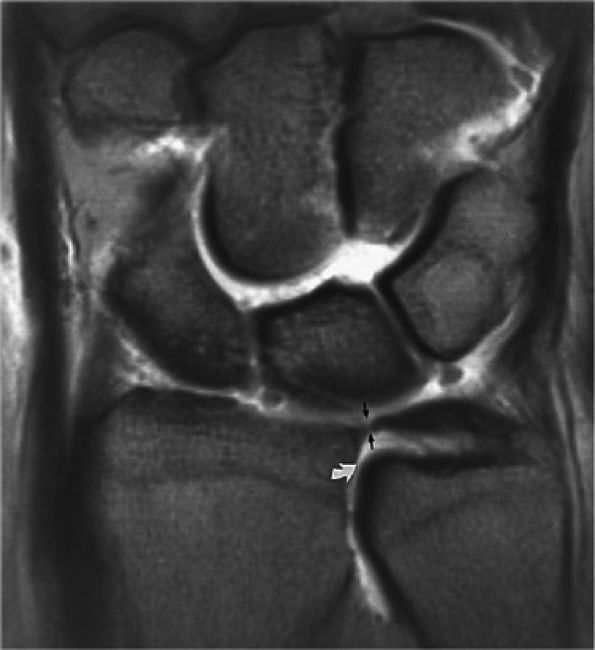

(ulnolunate) impaction syndrome, whereas ulnar negative variance may be associated with Kienböck's disease of the lunate. With distal radioulnar joint instability, the ulna is dorsally or volarly subluxed with respect to the radius, usually due to severe TFC complex tears.